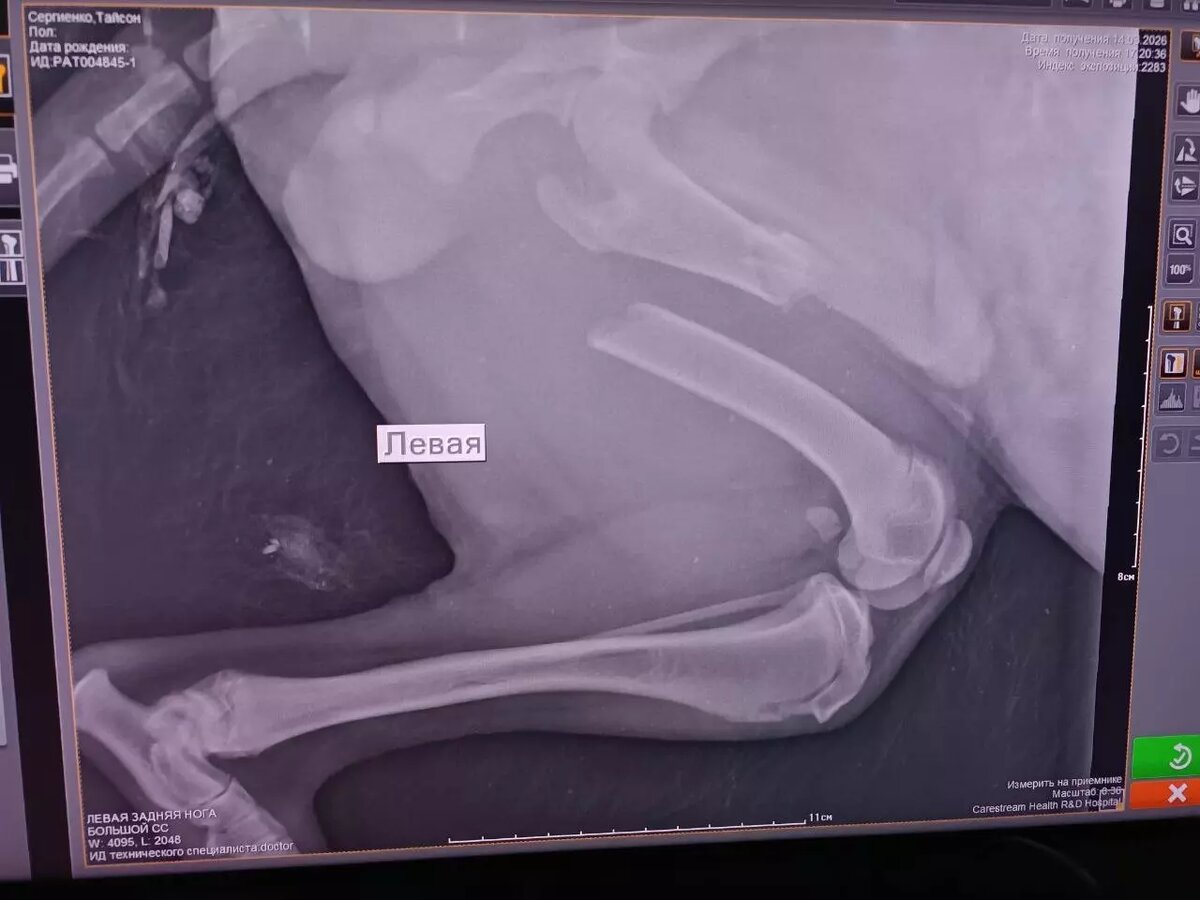

Волонтеры приюта договорились об операции для Тайсона (так назвали пса) в одной из клиник Ростова-на-Дону.

- Будут соединять переломы бедренной и седалищной костей со смещением, - уточнили волонтеры.